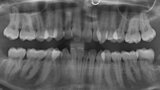

Ortodontická léčba komplexních případů malokluze pomocí průhledných alignerů